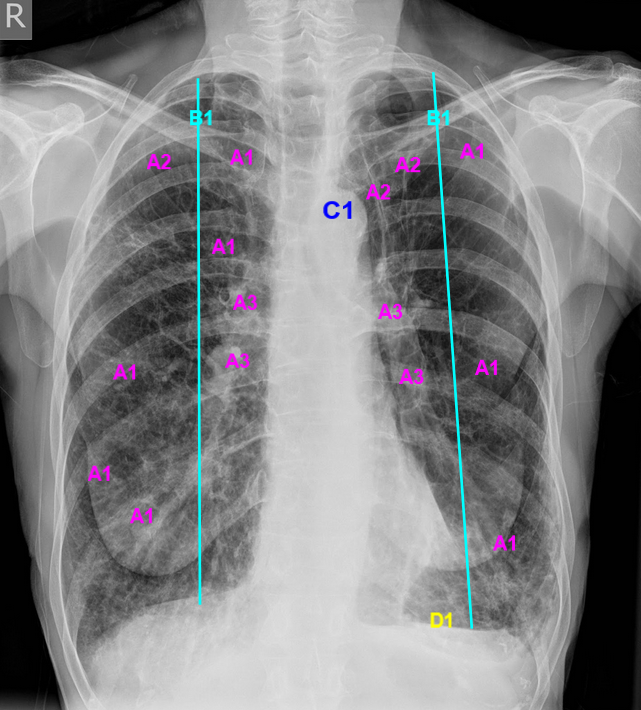

Fonte: BICKLE, Ian. Emphysema. Case study, Radiopaedia.org. 2017.

Fonte: BICKLE, Ian. Emphysema. Case study, Radiopaedia.org. 2017. s/emphysema-9.